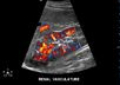

Beispiel: Ultraschallbild einer Niere mit farblicher Darstellung der Nierendurchblutung.

Neben Ultraschalluntersuchungen von Hals, Schilddrüse- und Abdomen (Bauch) werden auch Untersuchungen der Brust (Mammasonographie), des gesamten Bewegungsapparates (Gelenke, z.B. Schulter) und der Gefässe durchgeführt.

• Spezialuntersuchungen Ultraschall